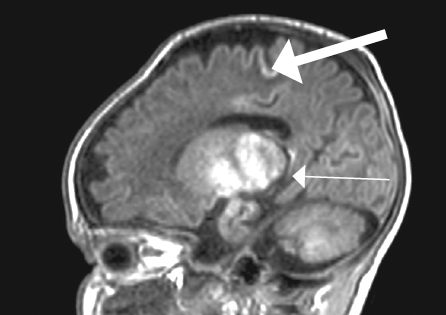

В статье кратко приведены литературные данные и описание клинического динамического наблюдения пациента с тяжелым гипоксическим повреждением головного мозга (от неонатального периода до 4-го месяца жизни) в условиях отделения реанимации и интенсивной терапии новорожденных. Представлены описание клинической картины, особенности пароксизмальных состояний и антиэпилептической терапии, динамика данных нейровизуализации, электроэнцефалографических феноменов, регистрируемых у пациента с церебральной депрессией и структурными церебральными повреждениями. Показана значимость электроэнцефалографического исследования в условиях отделения реанимации как информативного метода оценки церебральной активности у детей раннего возраста с синдромом угнетения центральной нервной системы. Дезорганизация фоновой активности, свидетельствующая о структурных церебральных повреждениях, длительное персистирование медленноволновой активности, выявление эпилептических изменений в виде генерализованных вспышек заостренных волн в диапазоне тета, паттерн альфа-комы, впоследствии сменившийся супрессией фонового паттерна у пациента, являются типичными электрофизиологическими нарушениями, регистрирующимися при тяжелой гипоксической энцефалопатии. В условиях ограничения возможностей визуальной диагностики пациента с нарушением сознания электроэнцефалография остается единственным методом получения информации о функциональном состоянии головного мозга, а данные, полученные при исследовании, — важным прогностическим критерием.